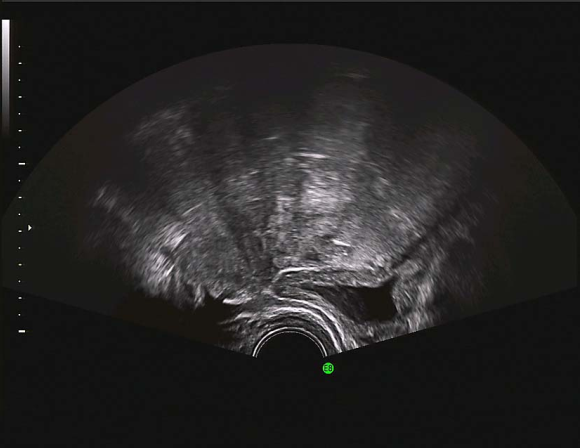

先天性无子宫经阴道超声